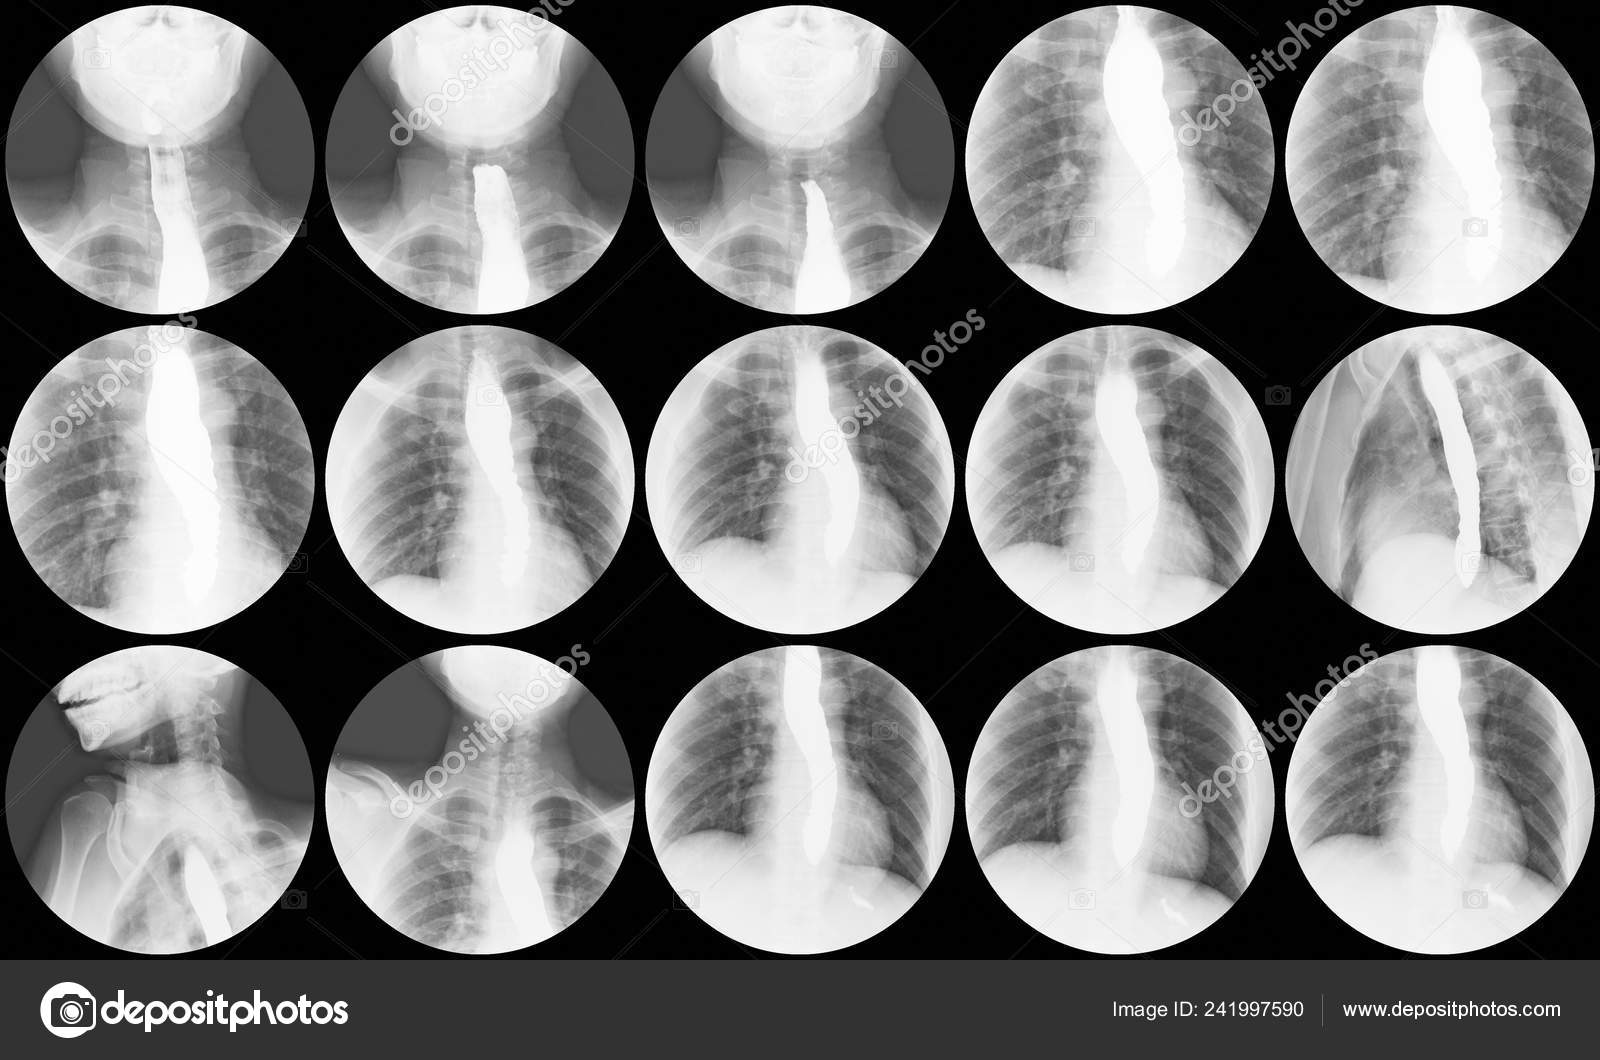

From depositphotos.com

Barium Swallow Ray Study Reveals Bird Beak Sign Distal Esophagus Bird Beak Sign X Ray The “bird’s beak” sign is a classic finding on esophagrams; The same appearance is also. bird’s beak sign. achalasia (primary achalasia) is a failure of organized esophageal peristalsis that causes impaired relaxation of the lower esophageal. the classic manifestation of achalasia on imaging is the “bird beak sign,” referring to the tapering of the inferior. the. Bird Beak Sign X Ray.